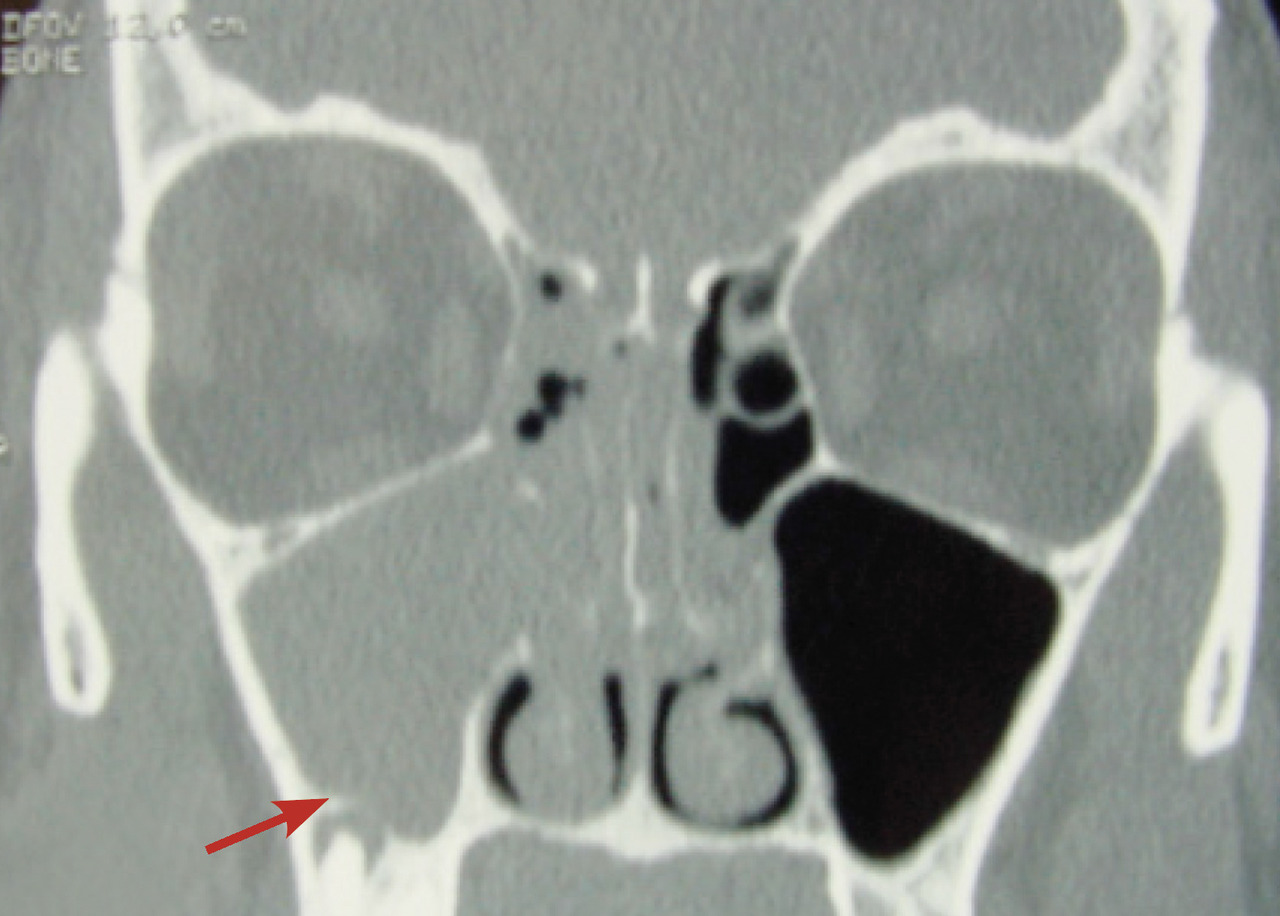

• forme collectée périorbitaire, définie par la présence d’une collection entre la paroi interne d’orbite et la péri­orbite (fig. 2), suspectée devant l’apparition d’une exophtalmie douloureuse, avec parfois une discrète limitation de la mobilité oculaire ;

Dans les sinusites maxillaires où l’origine dentaire est suspectée, il est également nécessaire de prescrire un scanner du massif facial (fig. 3) [souvent complété par un dentascanner, un panoramique dentaire et/ou des clichés rétroalvéolaires] et de faire pratiquer un bilan odontologique.